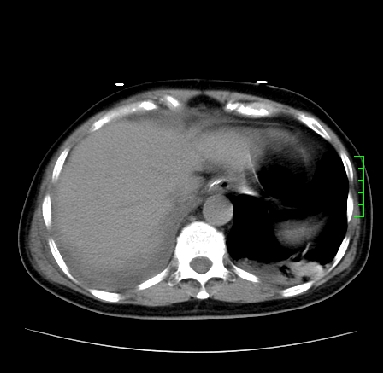

icu病人,几天都没明确诊断。m,76y,咳嗽、咳痰1周,伴气促,右胸痛入院,pe:t38.3c p135 r25 bp135/85。双肺可闻及大量湿罗音,心、腹未见明显异常。诊断:1心衰?2肺部感染?3冠心病?

11号ct